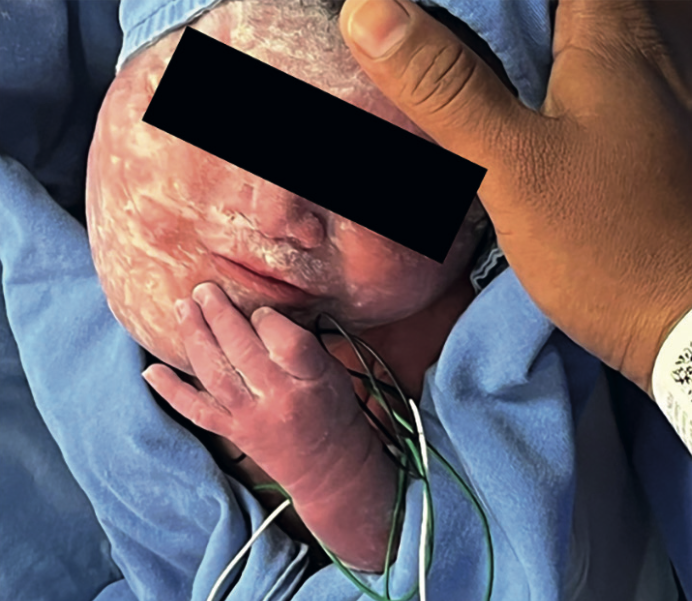

Paciente de 28 años, con diagnóstico a las 27 semanas de feto con tumoración y polihidramnios. En el ultrasonido y resonancia magnética, a la altura del cuello, se advirtió una tumoración anterior, derecha, de contenido quístico y sólido (mixta) de aproximadamente 9.16 cm x 6.94 cm x 7.40 cm sin afectar la tráquea. A la aplicación del Doppler color la tumoración se observó sumamente vascularizada. El embarazo finalizó por cesárea, a las 37 semanas, con obtención de un recién nacido masculino, Apgar 8-9. Previo drenaje se procedió a la escleroterapia en tres ocasiones, con dicloxacilina. Se dio de alta del hospital a los 12 días, con aplicación de un cuarto ciclo de escleroterapia. Continuó en control en la consulta externa. Figura 3 y Cuadros 1 y 2

<strong>Figura 3</strong>

Figura 3. Recién nacido con lesión en el hemicuello derecho. En la resonancia magnética se advirtió una lesión multiquística que afectaba el piso de la boca, con extensión a la hipofaringe y mediastino.